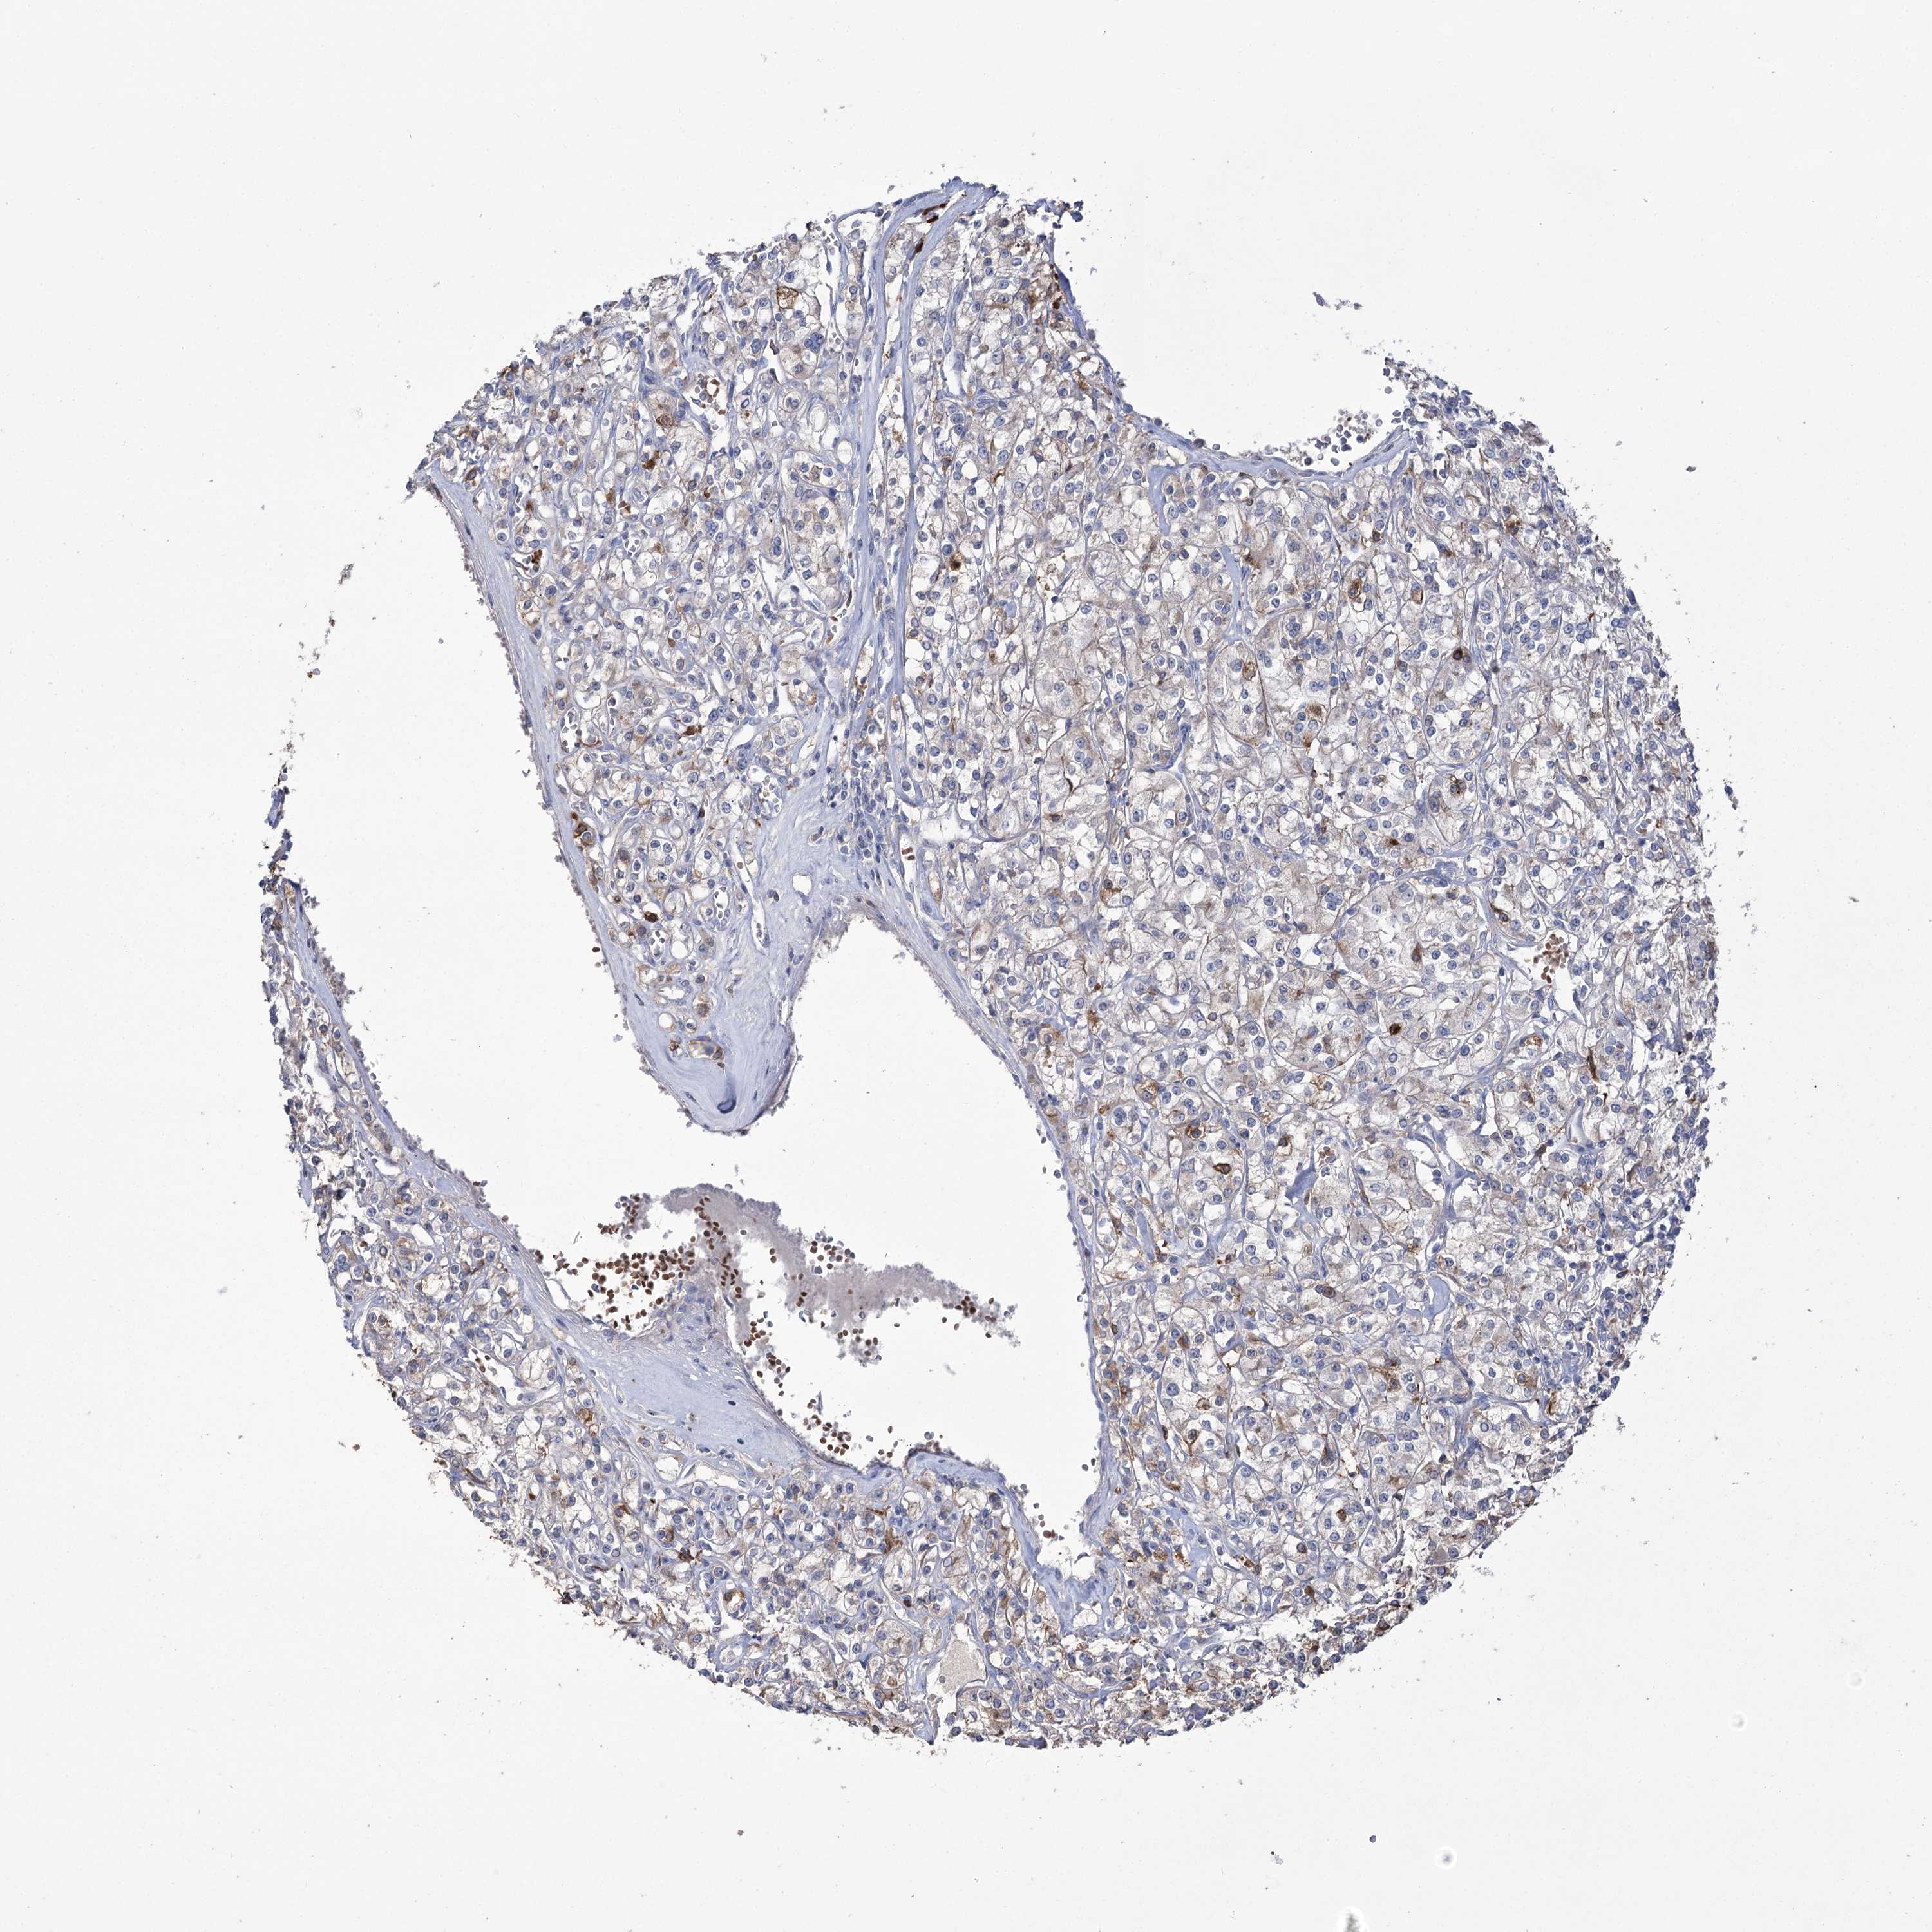

KIDNEY RENAL CLEAR CELL CARCINOMA (VALIDATION) - Interactive survival scatter ploti

The Survival Scatter plot shows the clinical status (i.e. dead or alive) for all individuals in the patient cohort, based on the same data that underlies the corresponding Kaplan-Meier plots. Patients that are alive at last time for follow-up are shown in blue and patients who have died during the study are shown in red.

The x-axis shows the expression levels (FPKM) of the investigated gene in the tumor tissue at the time of diagnosis. The y-axis shows the follow-up time after diagnosis (years). Both axes are complimented with kernel density curves demonstrating the data density over the axes. The top density plot shows the expression levels (FPKM) distribution among dead (red) and alive patients (blue). The right density plot shows the data density of the survived years of dead patients with high and low expression levels respectively, stratified using the cutoff indicated by the vertical dashed line through the Survival Scatter plot. This cutoff is automatically defined based on the FPKM cutoff that minimizes the p-score. The cutoff can be changed by dragging the vertical line or by entering a cutoff value in the square labeled "Current cut-off".

Under the Survival Scatter plot the p-score landscape (black curve; left axis) is shown together with dead median separation (red curve; right axis). Dead median separation is the difference in median mRNA expression between patients who have died with high and low expression, respectively. It is calculated as follows: median FPKM expression of dead patients with high expression - median FPKM expression of dead patients with low expression. This is intended to aid the user in visually exploring custom cutoffs and the associated p-scores and dead median separation.

Individual patient data is displayed and can be filtered by clicking on one or more of the category buttons on the top of the page. Categories describing expression level and patient information include: high, low, alive, dead, female, male and tumor stages. The scale of the x-axis can be toggled between linear and log-scale by clicking on the "x log" button. Mouse-over function shows TCGA ID, patient information and mRNA expression (FPKM) for each patient.

& Survival analysisi

Kaplan-Meier plots summarize results from analysis of correlation between mRNA expression level and patient survival. Patients were divided based on level of expression into one of the two groups "low" (under cut off) or "high" (over cut off). X-axis shows time for survival (years) and y-axis shows the probability of survival, where 1.0 corresponds to 100 percent.

ZNF622 is not prognostic in Kidney Renal Clear Cell Carcinoma (validation)

Best expression cut offi

Based on the FPKM value of each gene, patients were classified into two groups and association between prognosis (survival) and gene expression (FPKM) was examined. The best expression cut-off refers the FPKM value that yields maximal difference with regard to survival between the two groups at the lowest log-rank P-value. Best expression cut-off was selected based on survival analysis .

When clicking on this number, the vertical dashed line indicating cut-off, the interactive survival plot, and the Kaplan-Meier curve will be adjusted to show results based on the best expression cut-off.

: 28.31

P scorei

Log-rank P value for Kaplan-Meier plot showing results from analysis of correlation between mRNA expression level and patient survival.

N/A

TCGA RNA samplesi

RNA-seq data is reported as average FPKM (number Fragments Per Kilobase of exon per Million reads), generated by the The Cancer Genome Atlas (TCGA) .

Normal distribution across the dataset is visualized with box plots, shown as median and 25th and 75th percentiles. Points are displayed as outliers if they are above or below 1.5 times the interquartile range. FPKM values of the individual samples are presented next to the box plot.

Average pTPM 35.0

Number of samples 100